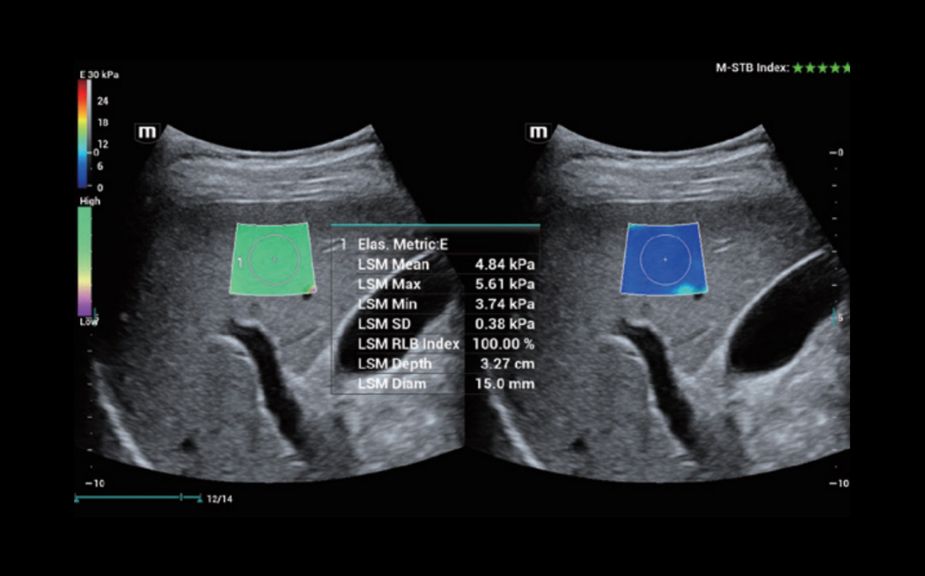

Innowacyjna Elastografia: HiFR STE

Do 10 razy szybsza cz?stotliwo?? od?wie?ania obrazu elastografii STE

Bardziej czu?e wykrywanie ruchu dla lepszej stabilno?ci i wi?kszej dok?adno?ci

HiFR STE - w?troba

Innowacyjna Elastografia: HiFR STE

Do 10 razy szybsza cz?stotliwo?? od?wie?ania obrazu elastografii STE

Bardziej czu?e wykrywanie ruchu dla lepszej stabilno?ci i wi?kszej dok?adno?ci

HiFR STE - w?troba